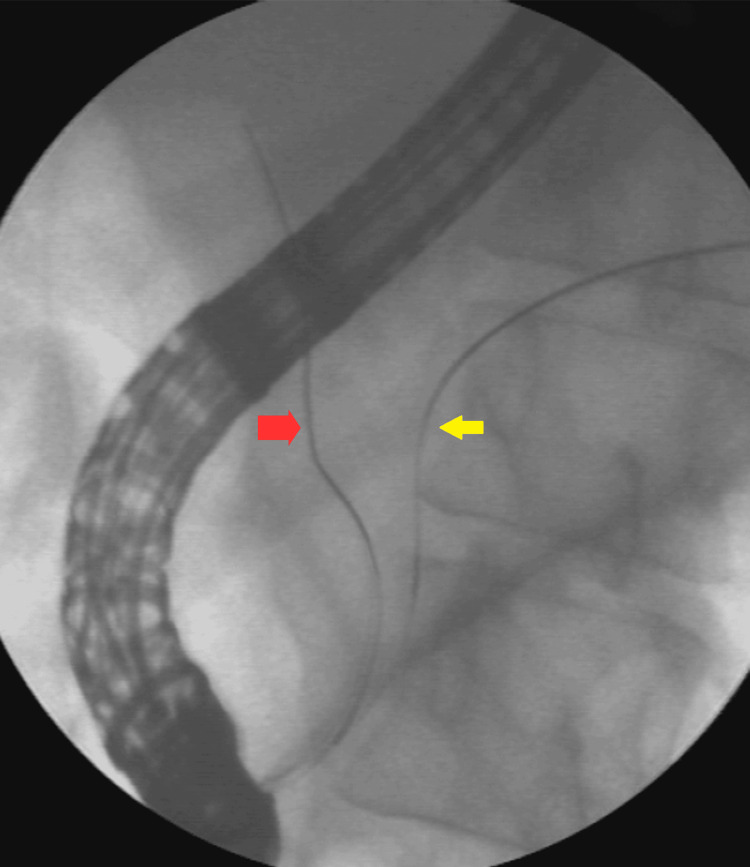

Imaging revealed 10-mm calculi in the dilated proximal CBD and a long narrowing of the distal CBD (Figure 3).